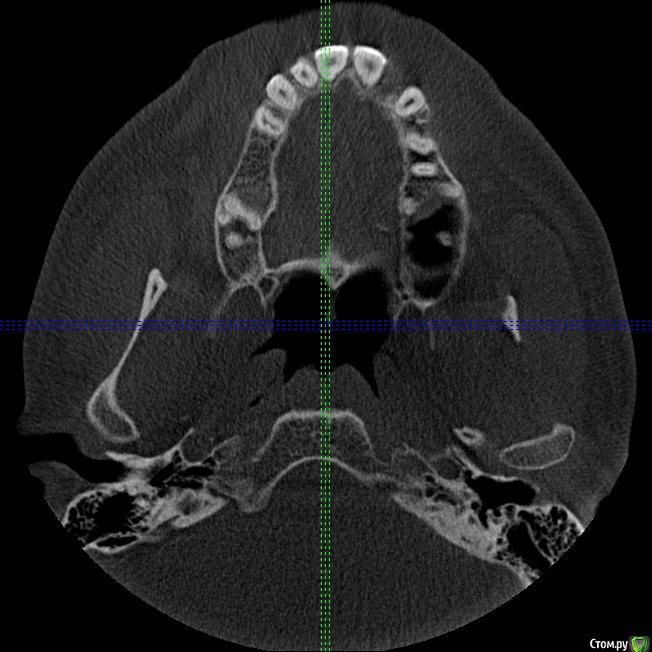

Секатор Опубликовано 4 октября, 2015 Поделиться Опубликовано 4 октября, 2015 (изменено) Здраствуйте,уже писал,но проблем много,но сча есть снимки зд(ссори за флуд).Начну издалека года два летом примерно неделю начили болеть зубы справа с отдованием в ухо и висок,оперативно ничего не делал(спас ал алкоголь),но я решил,что это 8-ки,и за зиму последнию все удалил,но отдования в висок и болезненность уха осталось,много времени прошло после удаления.Напряжение у виска и в области уха,взгляните на мою 6 справа,дно пазухи деформировано под её давлением,боли в области зуба нет-она причина?По лор все чисто,как будто болит зуб отдовая в ухо и висок,но без боли в области челюсти.Ближе к внутренней стенки пазухи и заходя на неё сформирован остроконечный конус дном пазухи,вследствии давлении корня зуба. Изменено 4 октября, 2015 пользователем Секатор 1 Ссылка на комментарий

Секатор Опубликовано 15 октября, 2015 Автор Поделиться Опубликовано 15 октября, 2015 Здравствуйте,сос...Рано поспешил радоваться,дело в следующем мне хорошо обкололи,и сверлили 47,положили мышьяк,ухо прошло на два часа,как в сказке был,но боль снова началась.Невралгия нерва по-любому есть,а вот причина!И,что где-то рядом с зубами.Все-таки планирую удалять 7 справа сверху,а ккак быть?Придётся методом тыка,у 7 корня небольшое утолщение слизистой пазухи,но вот ещё что,на уровне 5,6 была киста пазухи,прошла после удаления зубов. Ссылка на комментарий

Секатор Опубликовано 15 октября, 2015 Автор Поделиться Опубликовано 15 октября, 2015 (изменено) И,ещё раз прошу взглянуть смотрите,как деформирована внутреннеяя стенка пазухи зубом,у дна.Может корень подцепил,стенку пазухи? Изменено 15 октября, 2015 пользователем Секатор Ссылка на комментарий

kozloff Опубликовано 16 октября, 2015 Поделиться Опубликовано 16 октября, 2015 Поймите, с пазухой все хорошо, просто отлично, и с корнем верхнего зуба тоже. Удаляйте злосчастный мышьяк, пломбируйте каналы в пульпитом зубе и будет вам счастье! Ссылка на комментарий